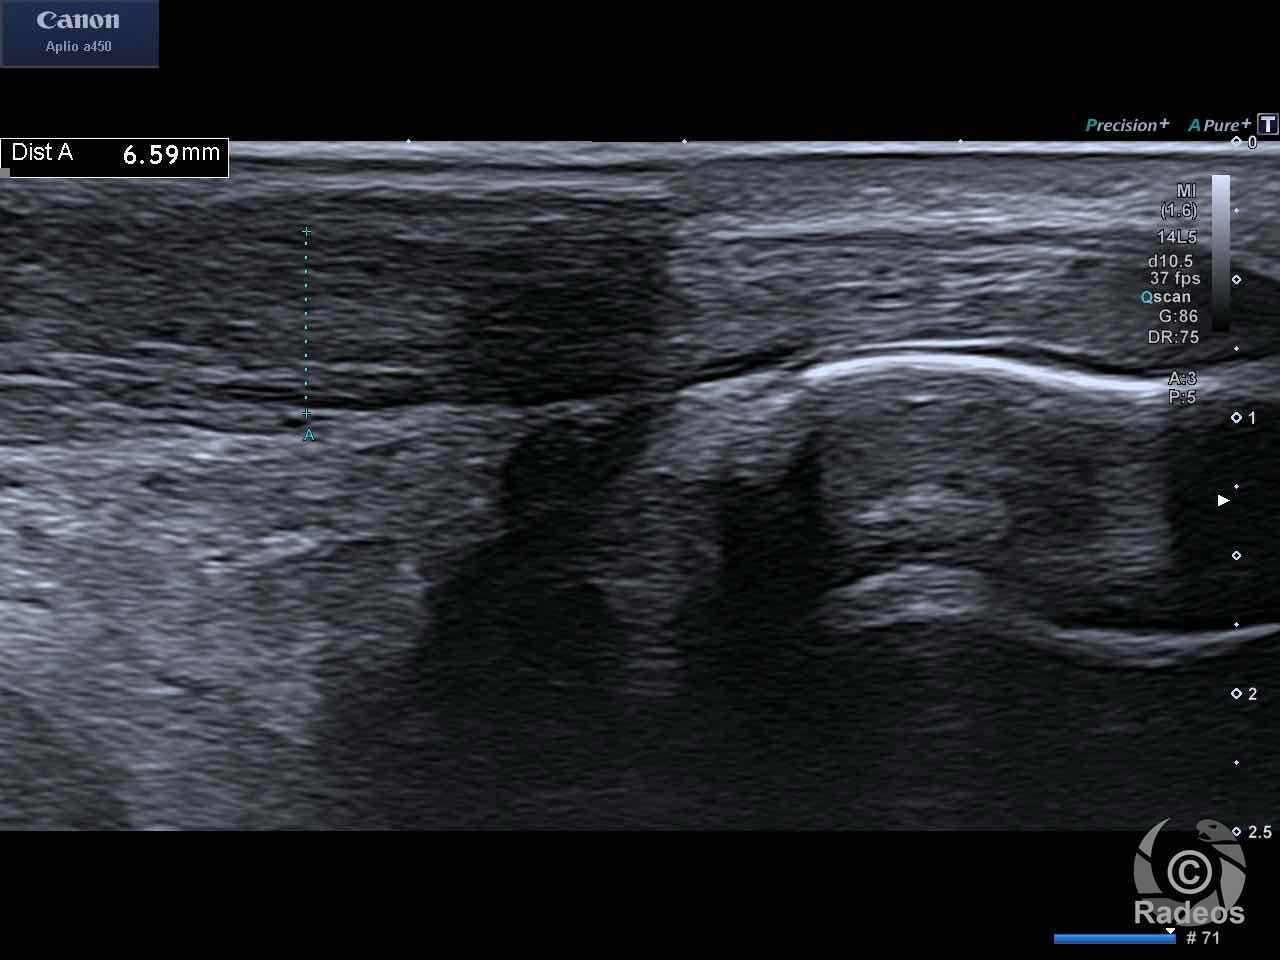

LE CAS DU MOMENT

Aspect IRM d'une fibromatose profonde de la paroi abdominale. Découverte fortuite d'un angiome hépatique gauche.